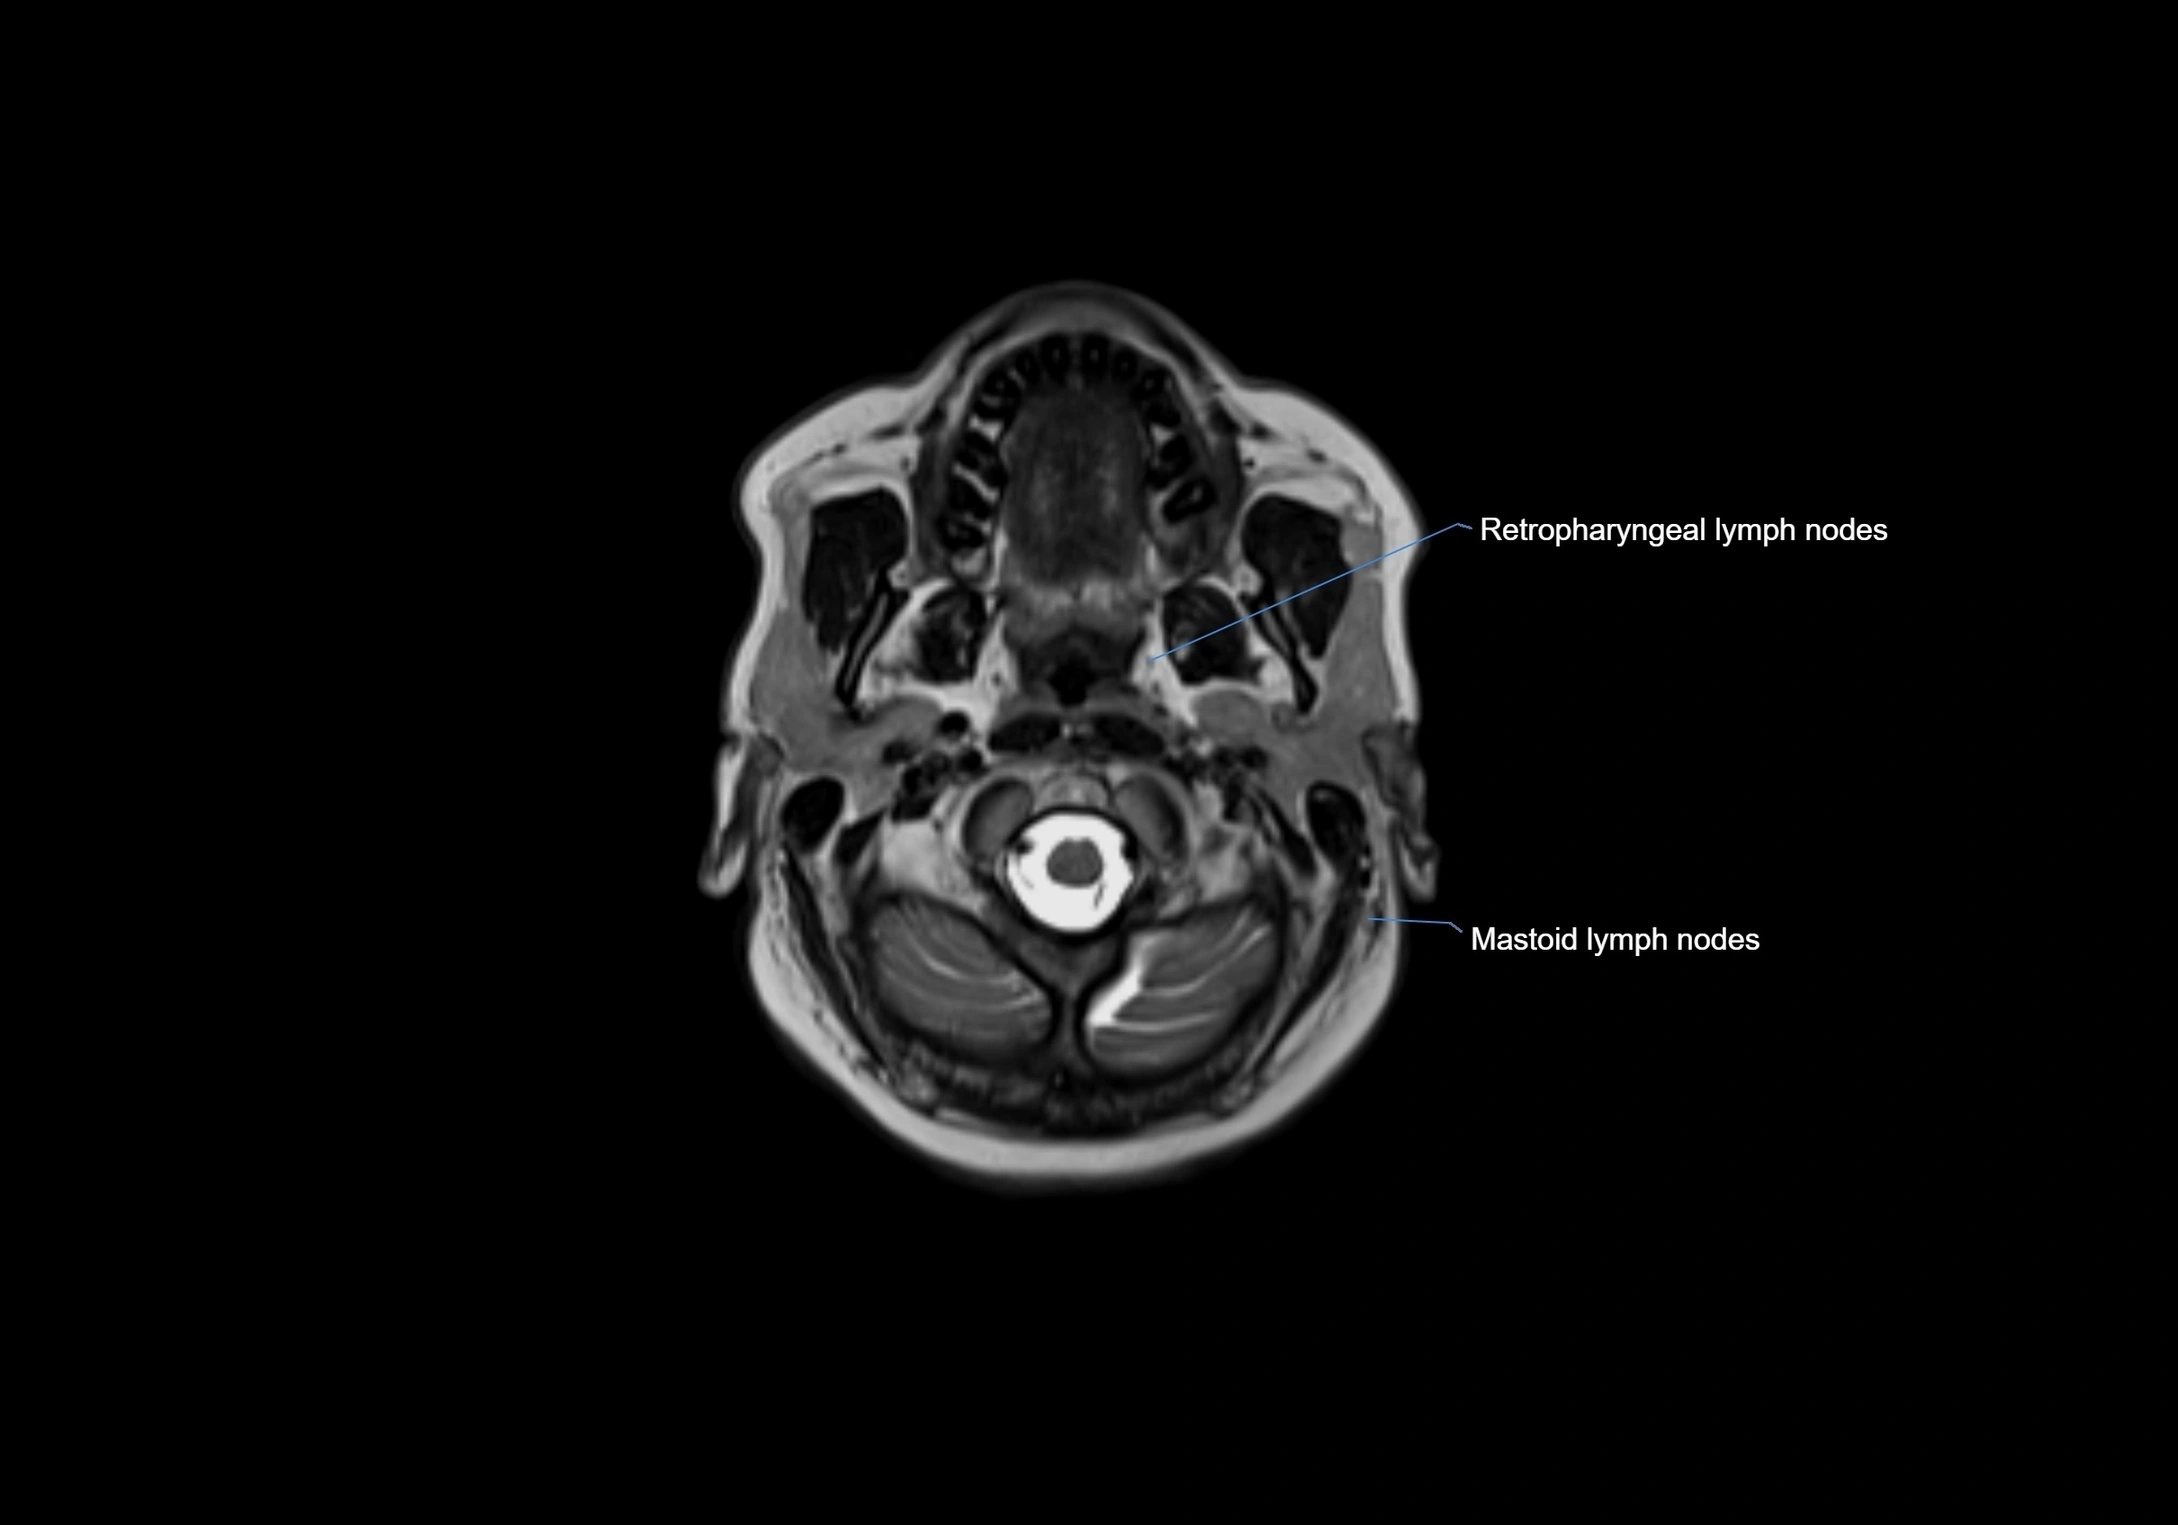

MRI Appearance

T1-weighted images:

• Normal accessory nodes appear as small, oval hypointense to intermediate signal structures within subcutaneous fat

• Surrounded by hyperintense fat, enhancing contrast for visualization

• Pathological nodes may appear enlarged or rounded, sometimes with cortical thickening

T2-weighted images:

• Nodes show intermediate signal, with surrounding fat bright

• Useful for detecting edema, inflammation, or infiltration

• Fatty hilum may appear slightly hyperintense relative to cortex

MRI images

image